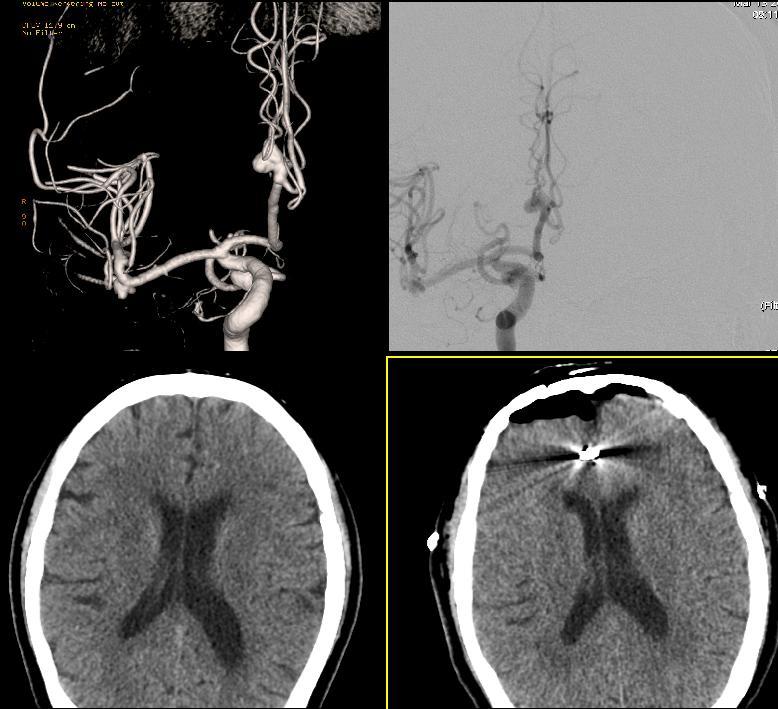

오늘 환자분은 간헐적 두통이 있어 외래 진료중 MRA검사에서 다발성

비파열성 뇌동맥류가 발견이 되시어 치료받게 되신 분이십니다.

먼저 영상의하과 권배주 교수님은 뇌혈관조영술을 통해 뇌동맥류의 위치와

크기, 모양, 주변 혈관과의 관계 등을 확인하시고 우선 파열의 가능성이 큰것

부터 치료를 하시로 결정하시어 오늘 수술을 받게 되신 분이십니다.

개두술을 통해 뇌동맥류가 위치해 있는 곳까지 안전하게 접근하시고 부풀어

오른 뇌동맥류를 확인하시고 클립을 이용해서 뇌동맥류의 목을 결찰하십니다.